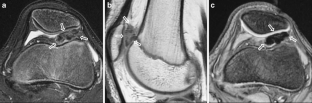

MR findings of synovial disease in children and young adults: Part 1

Synovial diseases in children can be classified into normal structures as potential sources of pathology (synovial folds: plicae, infrapatellar fat pad clefts); noninfectious synovial proliferation (juvenile idiopathic arthritis, hemophilic arthropathy, lipoma arborescens, synovial osteochondromatosis, pigmented villonodular synovitis, reactive synovitis), and infectious synovial proliferation, deposition disease, vascular malformations, malignancy (including metastasis) and intra-articular/periarticular cysts and cyst-like structures (ganglia). Familiarity with characteristic MR imaging findings of synovial diseases in children and young adults will enable a more confident diagnosis for earlier intervention and directed therapy. The first part of this paper will cover potential pathology of normal synovial structures as well as noninfectious synovial proliferation.